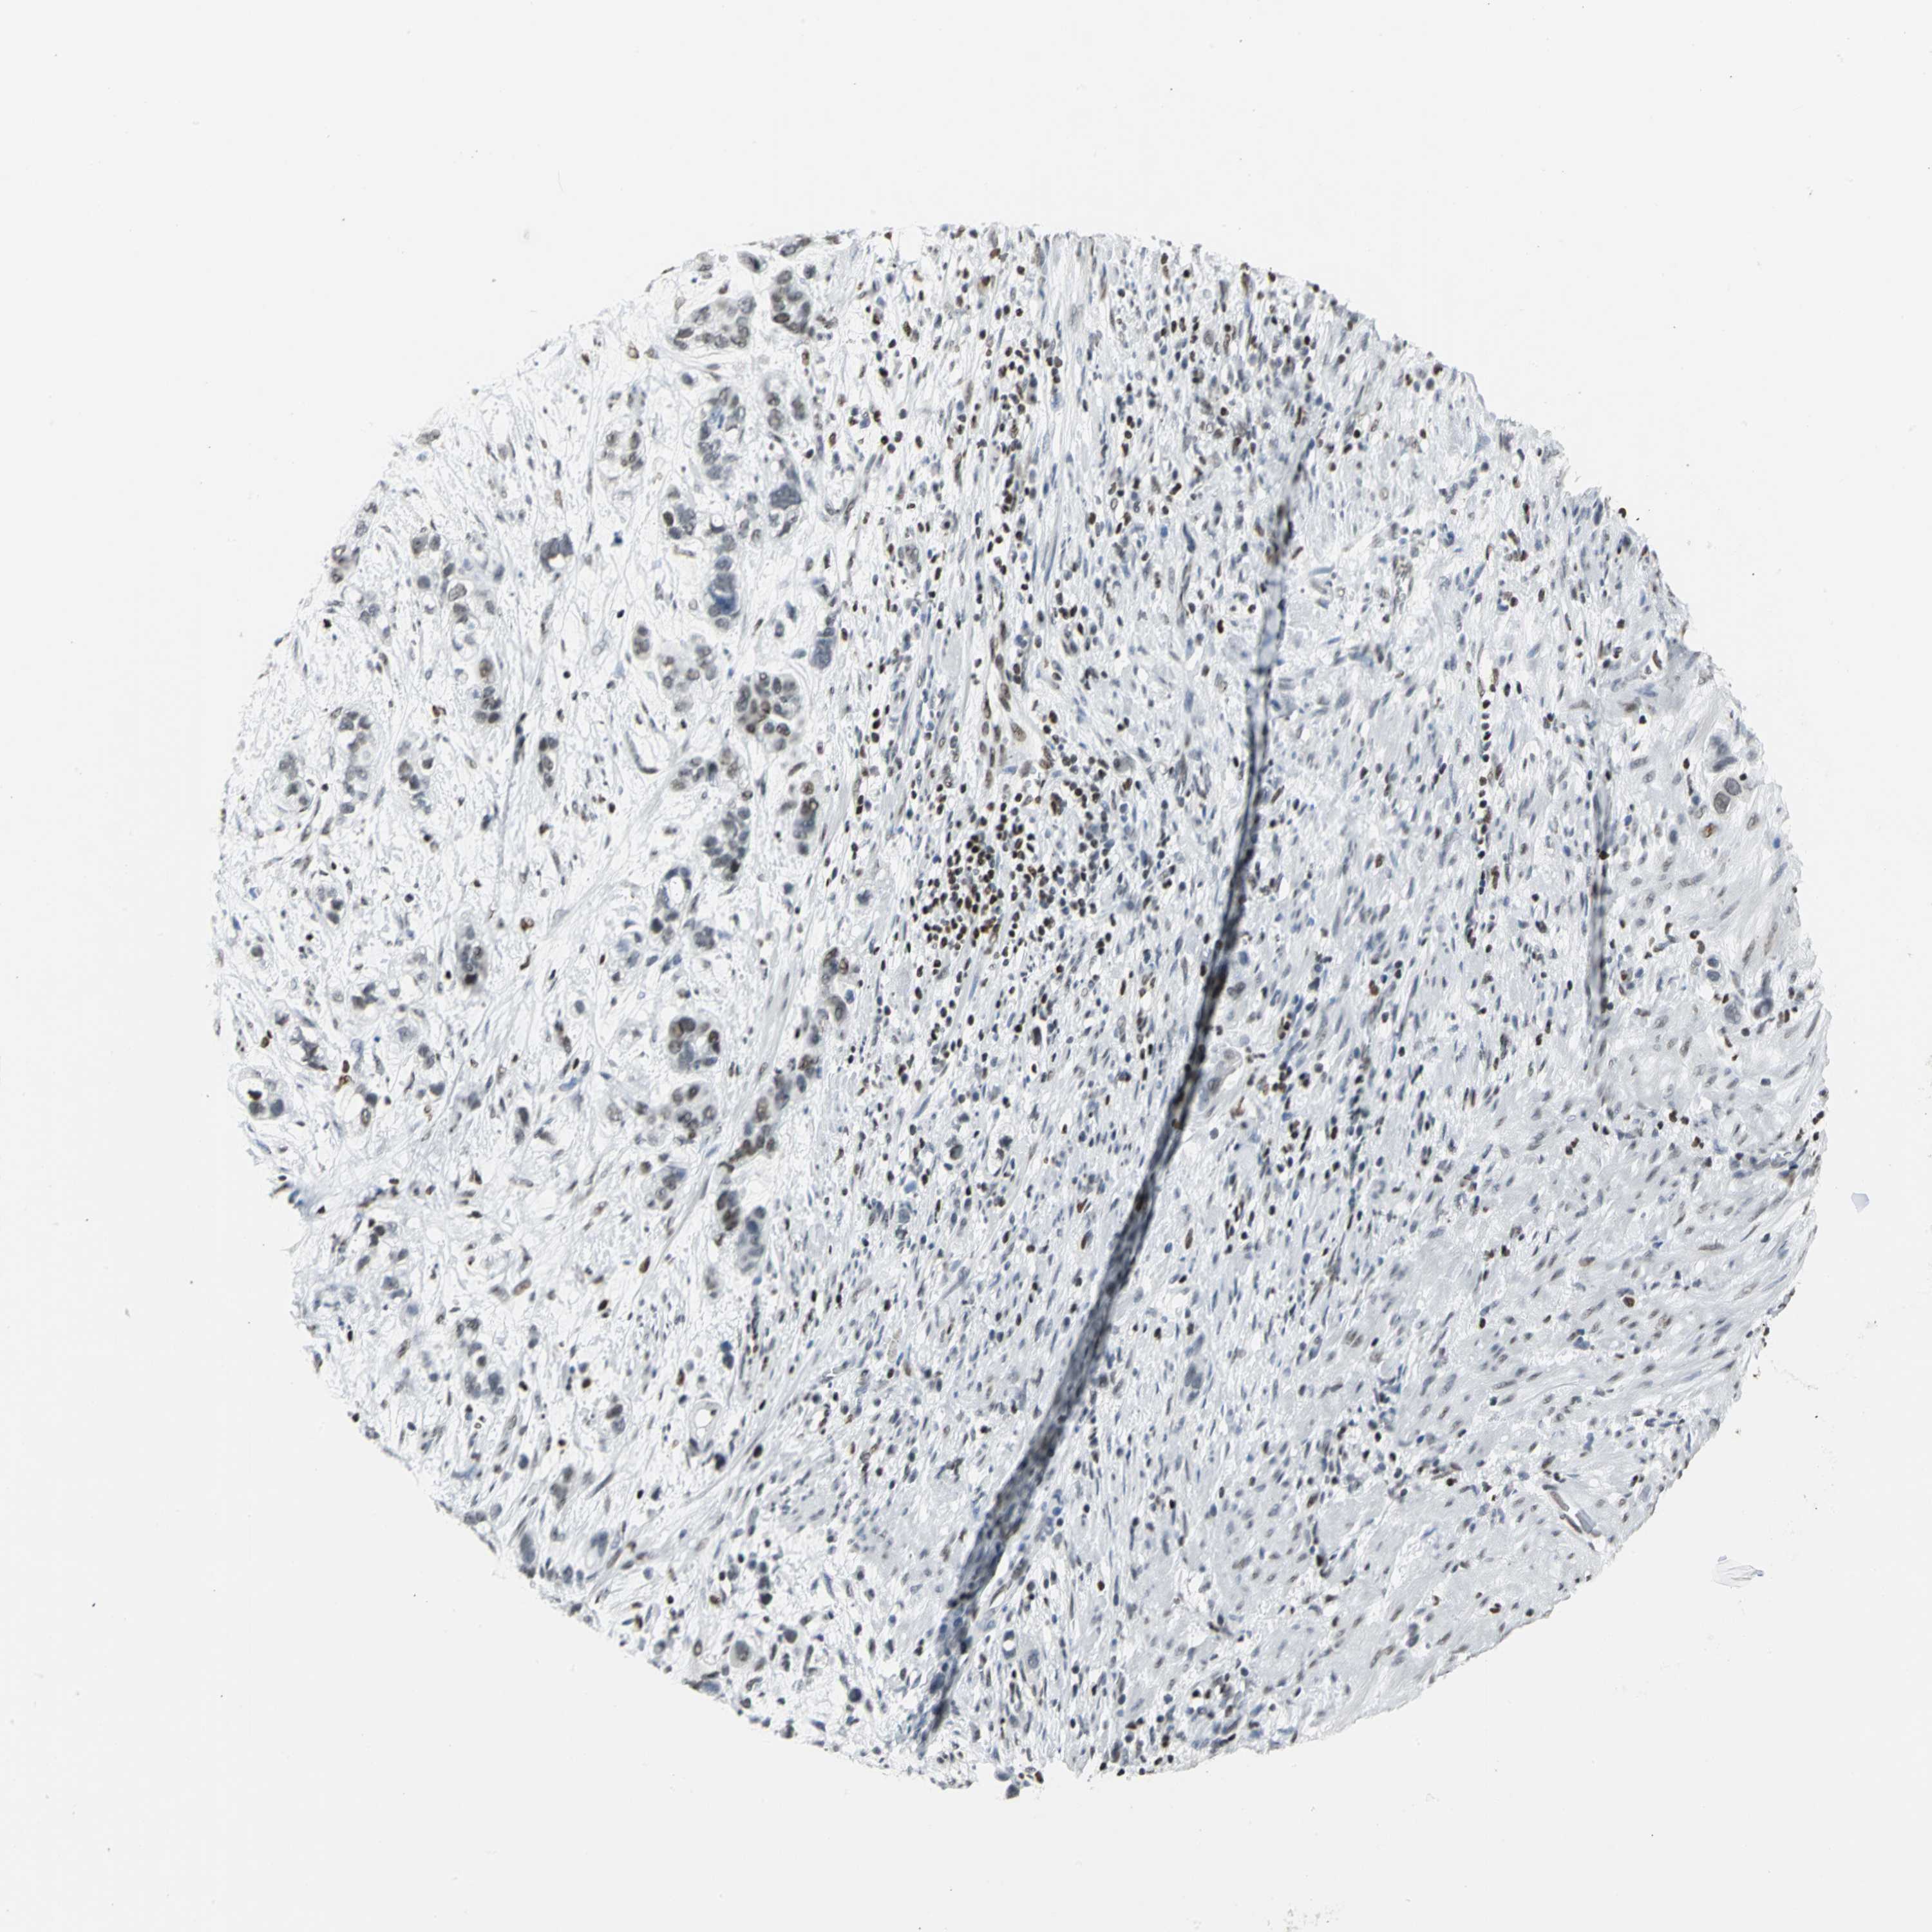

STOMACH CANCER - Protein expressioni

A mouse-over function shows sample information and annotation data. Click on an image to view it in a full screen mode. Samples can be filtered based on level of antibody staining by selecting one or several of the following categories: high, medium, low and not detected. The assay and annotation is described here.

Note that samples used for immunohistochemistry by the Human Protein Atlas do not correspond to samples in the TCGA dataset.

Antibody stainingi

Antibody staining in the annotated cell types in the current human tissue is reported as not detected, low, medium, or high, based on conventional immunohistochemistry profiling in selected tissues. This score is based on the combination of the staining intensity and fraction of stained cells.

Each image is clickable and will lead to virtual microscopy that enables deeper exploration of all samples and also displays staining intensity scores, fraction scores and subcellular localization as well as patient and tissue information for each sample.

Antibody HPA004911

Staining

High

Medium

Low

Not detected

Intensity

Strong

Moderate

Weak

Negative

Quantity

>75%

75%-25%

<25%

None

Location

Nuclear

Cytoplasmic/membranous

Cytoplasmic/membranous,nuclear

Adenocarcinoma, NOS

Adenocarcinoma, High grade